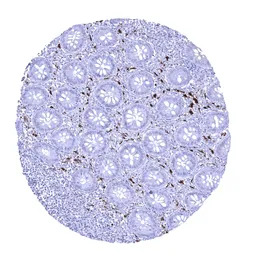

IHC-P analysis of human lymph node tissue section using GTX04452 Factor XIIIa antibody [MSVA-813R] HistoMAX.

Strong Factor XIIIa immunostaining of sinus histiocytes in a lymph node.